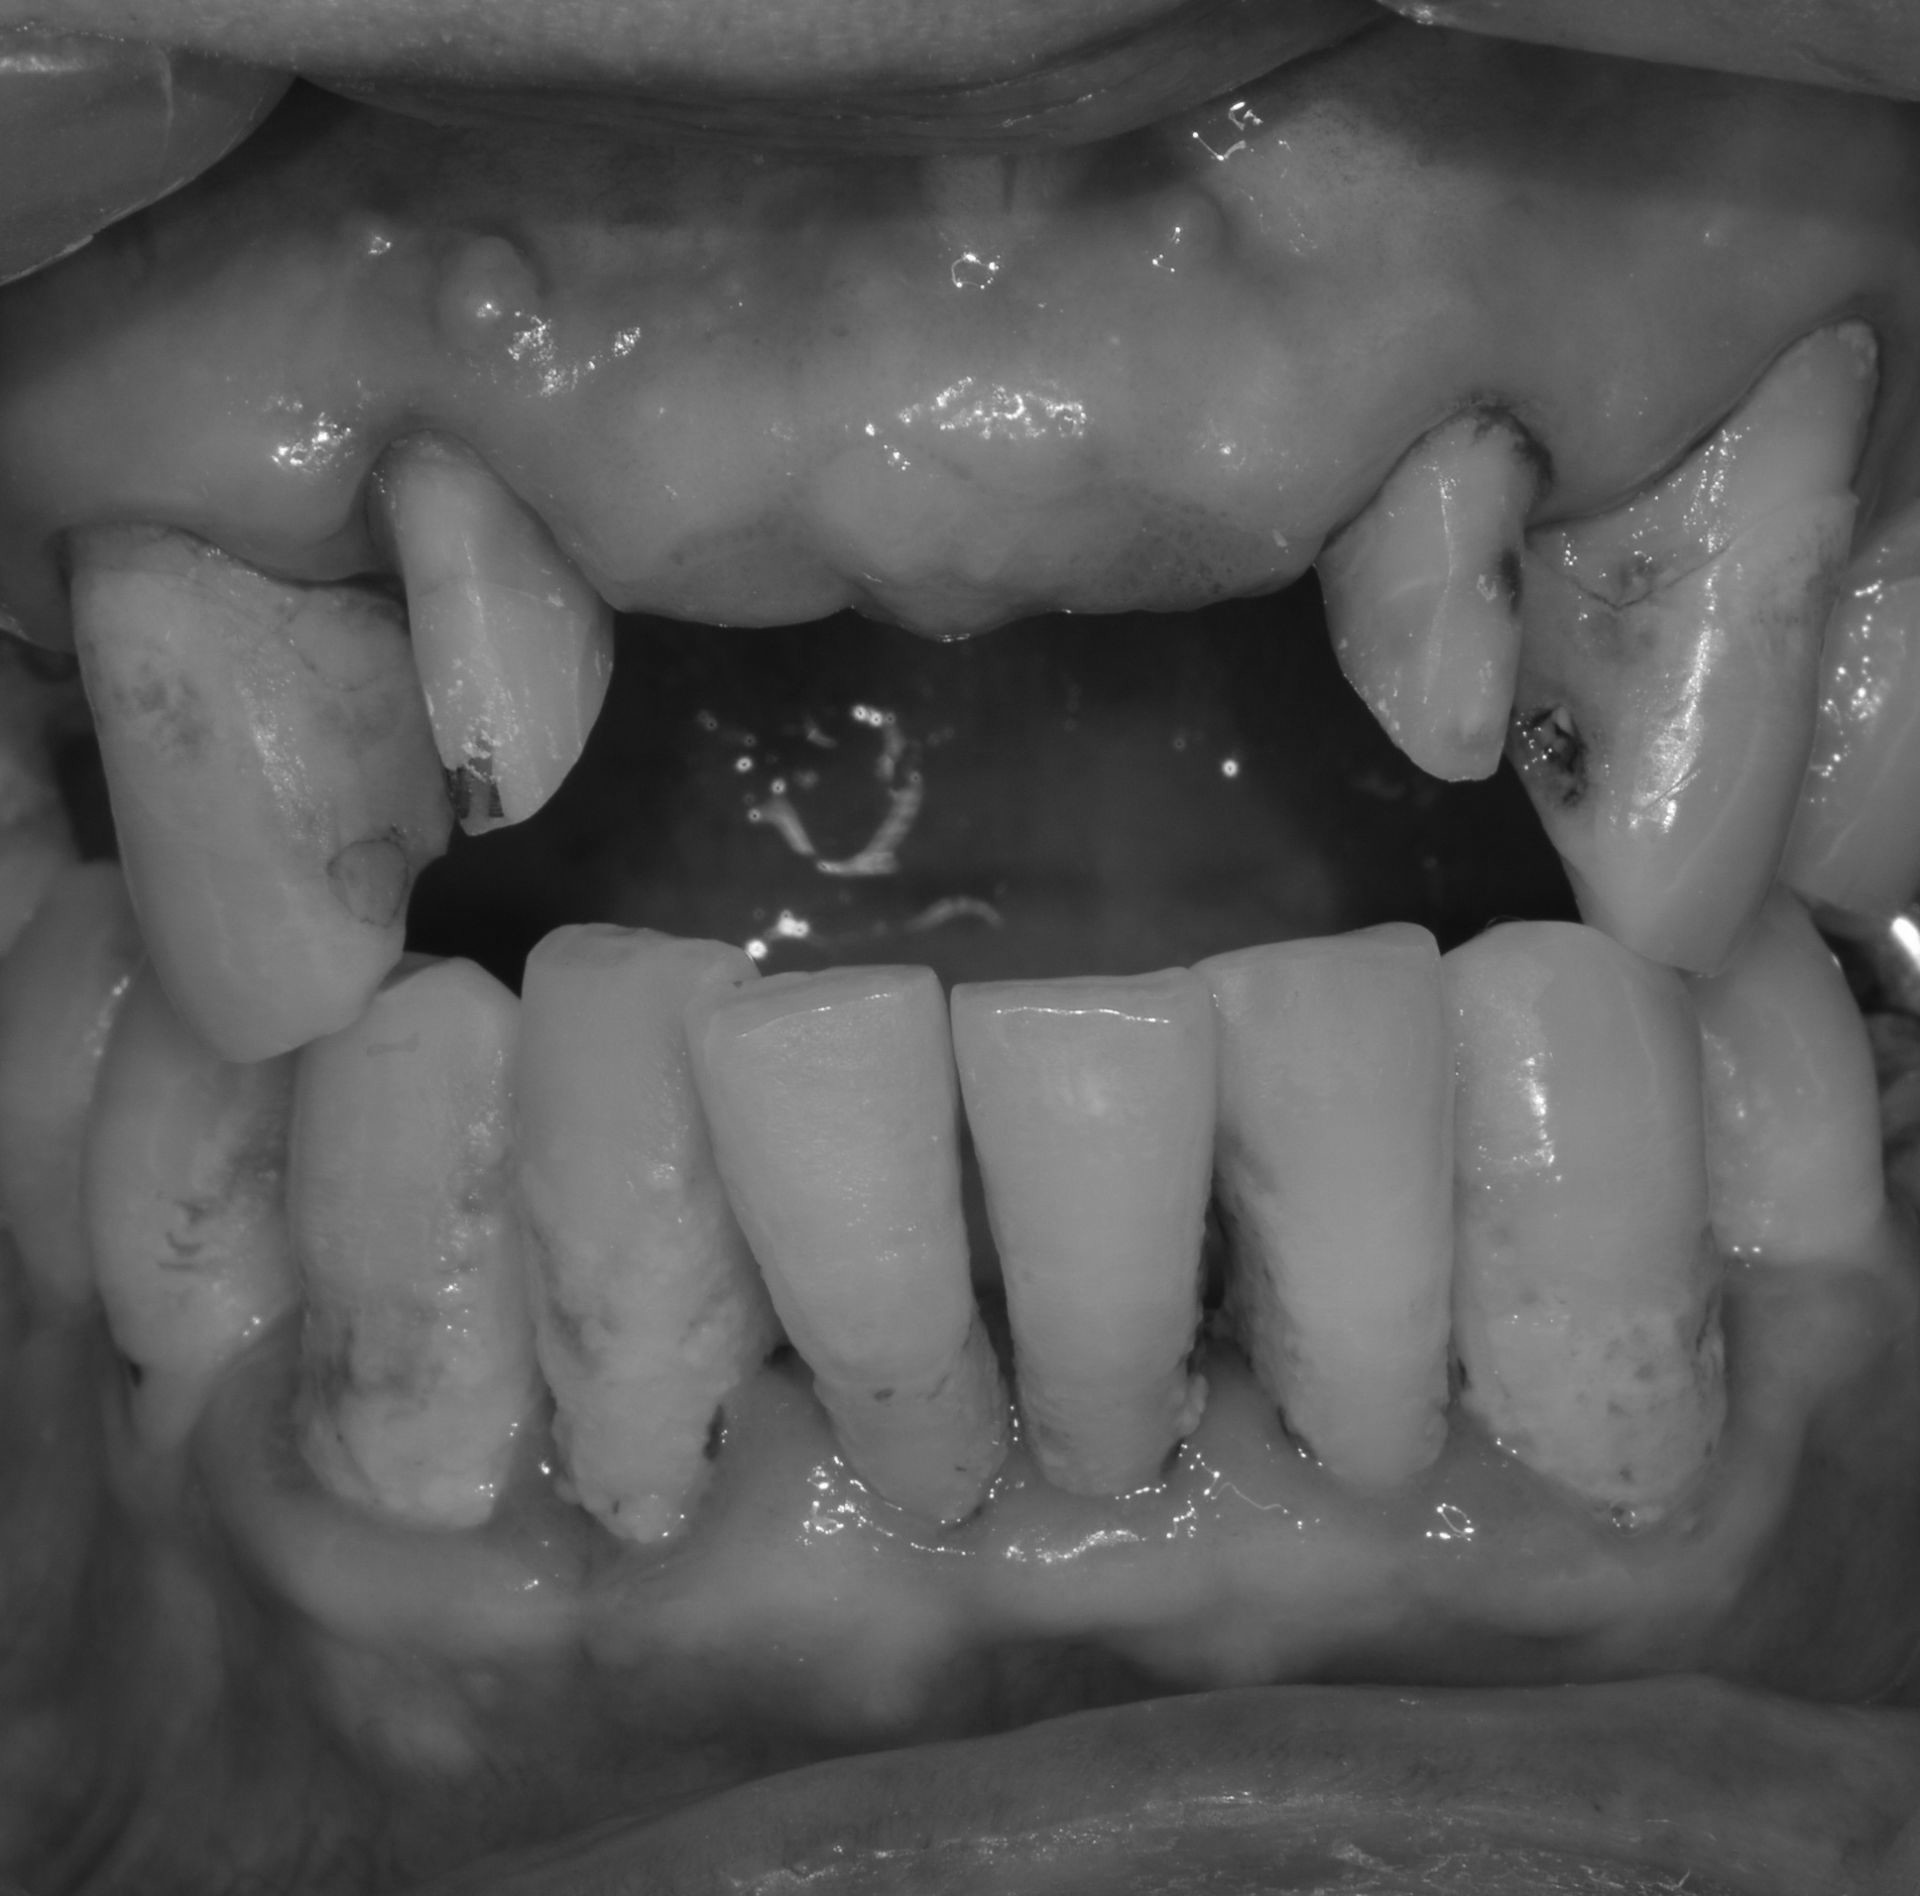

치아우식, 신경치료 및 치은성형술, 심미보철치료

치료 기간 2023. 11. 02 ~ 2023. 12. 20

확장 개원 후 마무리하신 환자분입니다. 앞니 기존 보철물을 하고 계셨지만 치아가 삭아서 보철물이 탈락해서 내원하셨습니다.

환자분께서는 뽑고 임플란트를 생각하고 오셨지만... “치아는 살릴 수 있다면, 살리는 게 좋다.”

간단한 잇몸 수술, 신경치료 후에 기둥을 세워 치아머리만 만들어진다면 충분히 살릴 수 있다고 판단하고 살리는 쪽으로 설명드렸습니다.

환자분들의 치아 하나하나를 소중히 생각하는 참조은치과입니다.

* 상기 사진은 본원 권대근 대표원장이 치료한 환자분의 동의를 받은 이미지 사진으로 실제와 차이가 있을 수 있습니다.